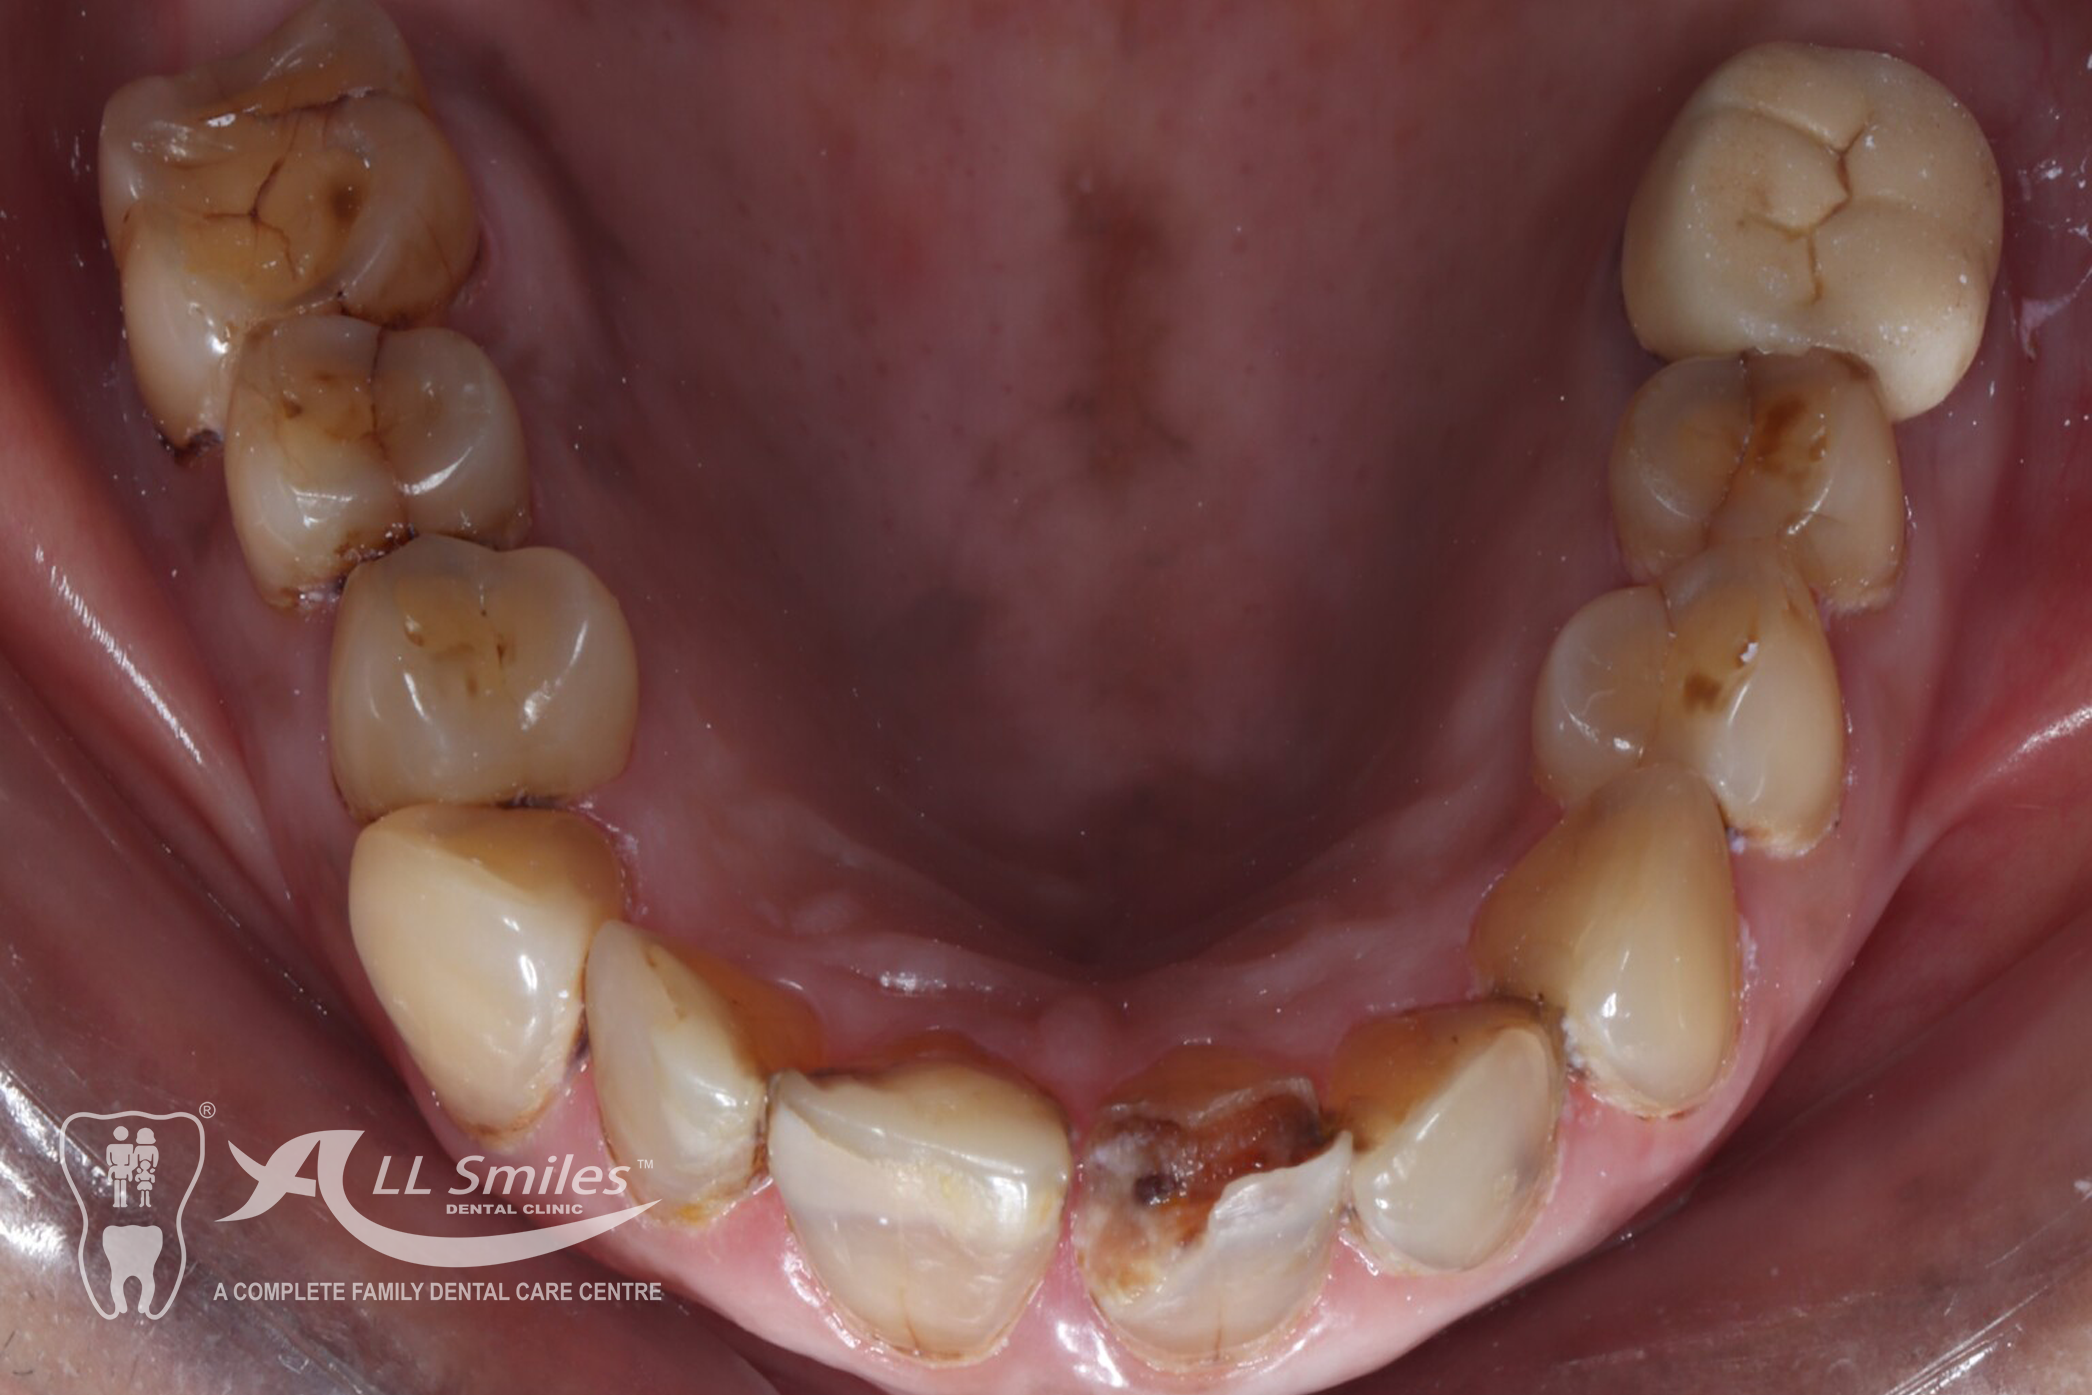

Root Canal Gallery